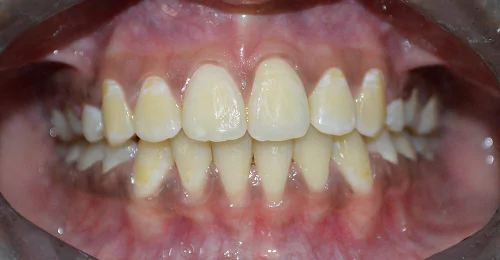

Anterior Crossbite Correction

Without Extraction Of Teeth

A young newly married female had crossbite in front teeth and when she smiled she felt her teeth appeared crooked. Being newly married she also had concerns regarding wearing braces. Assessing the situation, we advised ceramic braces and treated the condition without extracting or removing any teeth.

Pre Treatment

The treatment was completed successfully after a period of 18 months. Our patient is now embarked on her newly married life with more confidence.